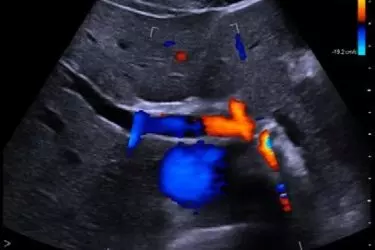

Ultrasound of the abdomen is used to diagnose gall stones, cbd stone, liver diseases, pancreatic stone or pancreatitis, kidney stones, urinary bladder problems, ovarian cyst, uterine fibroids, ureteric stones, intestinal obstruction or perforation, appendicitis. Almost 60-70% patients who come to the hospital with the complaint of pain abdomen, vomitting, menstrual disorders, diahorrea are advised to undergo an ultrasound scan of the abdomen. Ultrasound is one of the cheapest and most effective diagnostic tool. In order to get a quality ultrasound the combination of a good 3D Ultrasound Machine and an experienced radiologist is very important. The ultrasound machine at our centre is high quality 4D machines and all the probes have more than 10000 channels for crystal clear grey scale images. Stones of the size 2-3 mm are also visible with such high resolution probes. The best advantage of ultrasound scan is that it is free of any radiation and even a pregnant woman can undergo any number of ultrasound scans without causing any damage to her body or the foetus in her tummy. Ultrasound is an excellent modality for early detection of any kind of cancer in the body.

In order to achieve highest quality standards in the field of diagnostics, ideal combination of man and machine is needed. Suraj Diagnostics has installed the best in class technology when it comes to equipments like Ultrasound, Color Doppler and Digital X-Ray. Most advanced Ultrasound and Color Doppler from Philips Netherlands Affinity 50 is installed at Suraj Diagnostic Centres both at Sector-63, Gurgaon and Sohna. The 4D Ultrasound machine has all types of probes including 4D TVS probe and Cardiac Probe. All the machines are fully digital and give crystal clear images of the body part which is getting scanned.